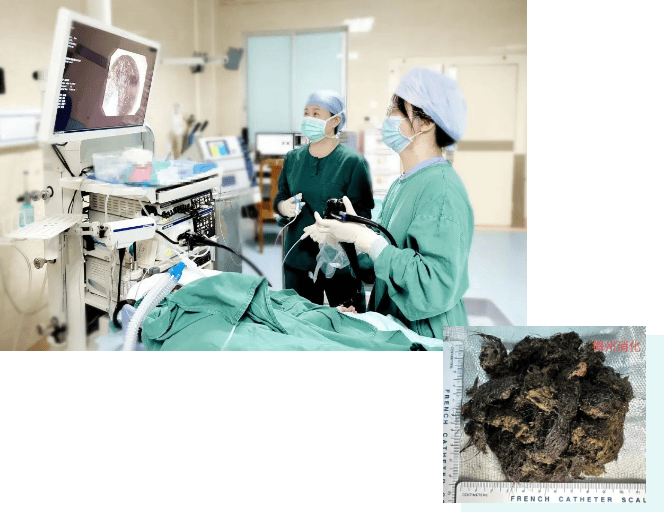

结果出来时,医生都惊呆了:小可的胃里,塞满了成团的头发,几乎占了胃容量的四分之三皇冠信用網在线注册。大量不能消化的物质,在胃酸的作用下发生变性,并与食物及其他物质结合形成团块,慢慢变成坚硬的“胃石”。

为了避免用手术方式去除头发团, 陈攸涛先让小可喝可乐软化“胃石”,再通过胃镜辅助取出头发,整个过程花了十几个小时,清理出的头发装了 两大盆皇冠信用網在线注册。